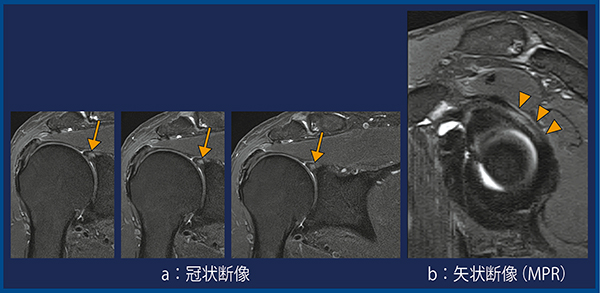

症例2は,上方関節唇損傷である。2D 1mm画像(図4)の冠状断像にて上方関節唇の異常信号を認め(a↓),MPRの矢状断像では前後方向の関節唇損傷の範囲が明瞭であった(b▼)。

図4 症例2:上方関節唇損傷